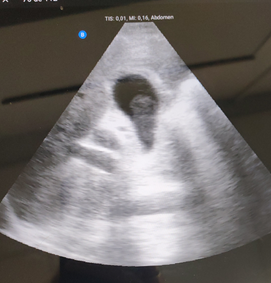

ECOGRAFIA CLÍNICA:  Se aprecia vesicular biliar bien repleccionada con imagen en su interior redondeada, hipoecoica, sin sombra, Murphy ecográfico positivo.

La clínica ya orienta el diagnostico pero la Ecografia filia el origen.

Lo llamativo para mi del caso fue visualizar un calculo biliar sin sombra (calculo blando) , saber de su caracteristicas ecograficas y tenerlo como opción diagnóstica.